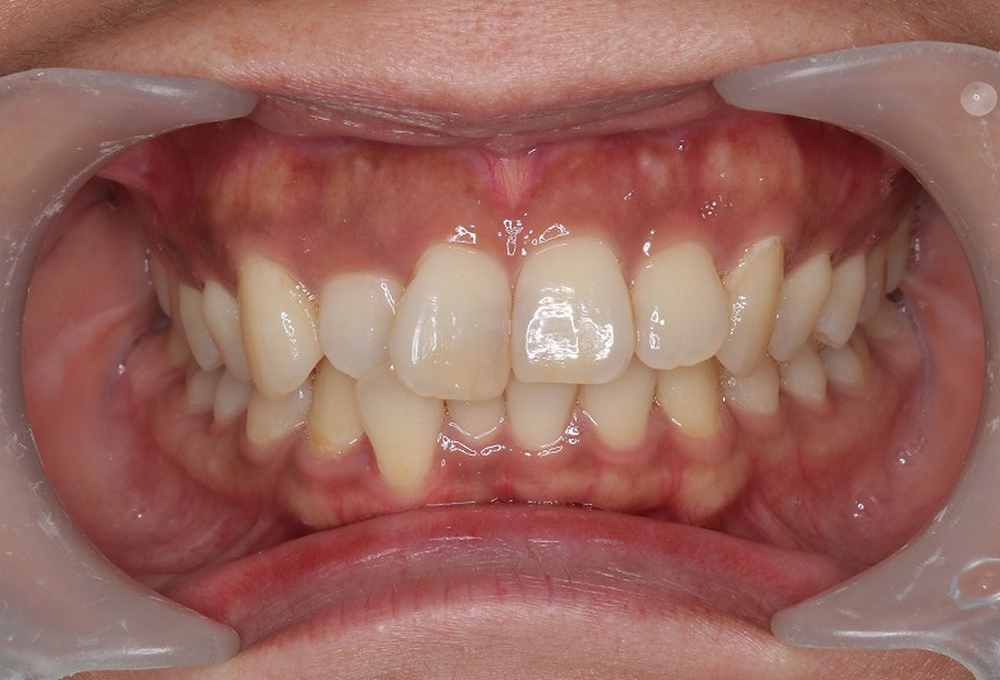

③正面観